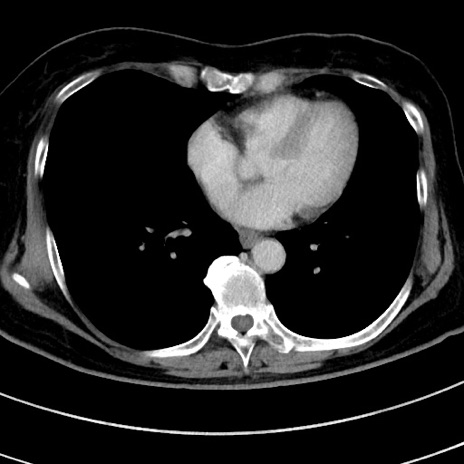

冠状断像